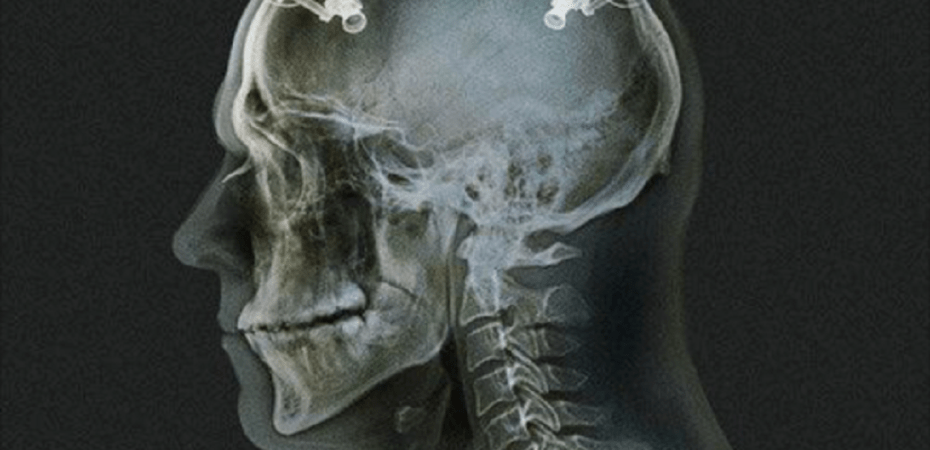

During this session, their brains were connected to an fMRI machine that monitored their neurological activity. So was an artificial intelligence program that was aimed to read the brain activity of the volunteers and capture a mathematical description of the shown faces.

The data used by the mind-reading system to reconstruct faces was based on the activity in two brain areas – the angular gyrus (ANG) and the occipitotemporal cortex (OTC). The ANG is responsible for spatial awareness, memory formation, number and language processing while the OTC’ function has to do with the processing of visual stimuli.